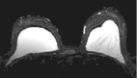

Left images show intracapsular rupture in the left implant ("linguini sign").   Right images from a contrast dynamic scan show an intensely enhancing mass adjacent to a right implant.

High-resolution MRI is extremely accurate for diagnosing silicone and saline implant rupture.   The so-called "linguini sign" refers to serpiginous thin lines seen with intracapsular rupture (left 3 images above).   Various new "silicone techniques" can also detect extracapsular extravasation of silicone.